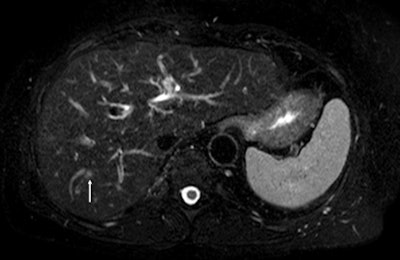

Based on extensive imaging workup and patient clinical status in cases of colorectal liver metastases, radiologists and hepatobiliary surgeons must discuss whether the patient is resectable, unresectable, or borderline. In unresectable or borderline patients, radiologists should evaluate tumor response to select the best treatment. In the future, morphologic and functional imaging may anticipate the histologic response.

"In colorectal liver metastases, the main goals are to assess resectability, to consider secondary resectability, and to evaluate tumor response," he said. "CT and MR imaging are essential, MR being the most sensitive for tumor detection. Further work has to be done to better analyze tumor response using functional imaging."